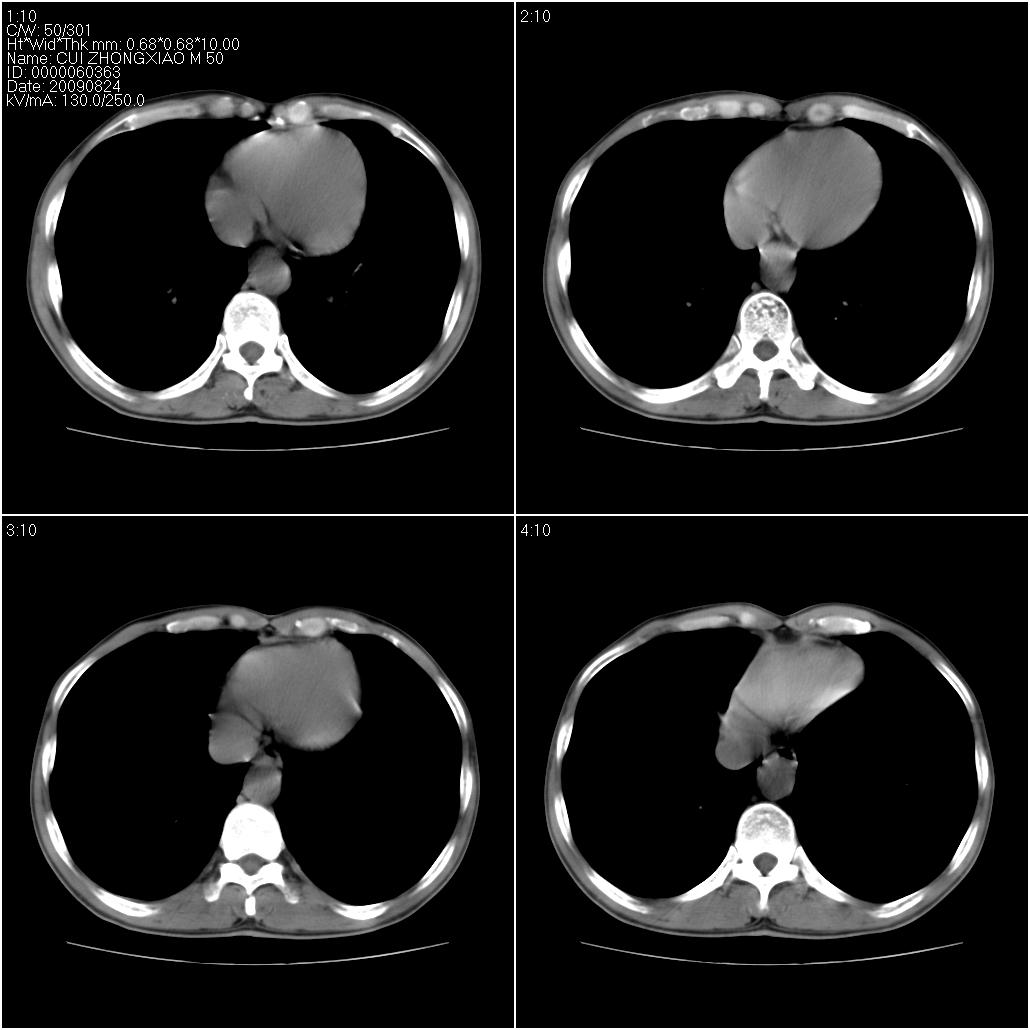

标题: CT21851:男性,50岁。间断性咳嗽半年。 [打印本页]

标题: CT21851:男性,50岁。间断性咳嗽半年。

左侧感染!不排除局限性肺泡蛋白沉着症!

磨玻璃样改变(左肺及右肺上叶前段),边缘模糊,考虑炎症,建议严格抗炎治疗后复查除外肺泡蛋白沉积症或肺泡出血(病人有咯血吗) 肺泡癌.

肝左叶肝内胆管扩张,进一步检查.